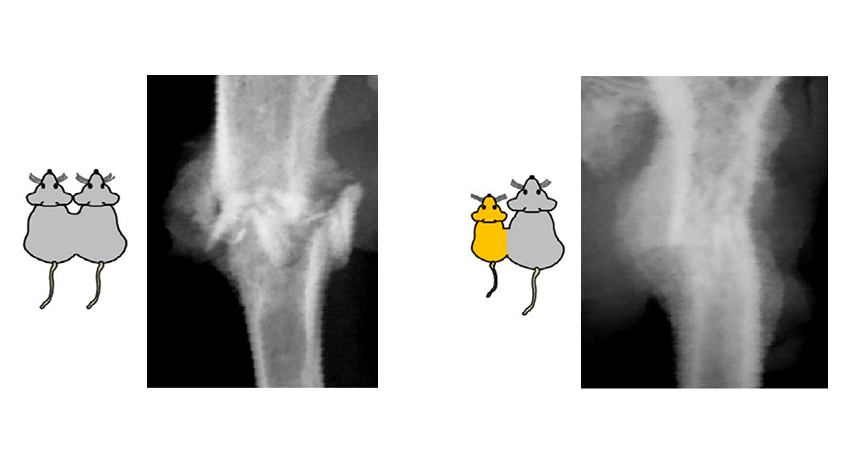

Surgically linking the circulatory system of old mice (gray) to young mice (yellow) boosts healing of broken bones (X-ray at right), compared with linking two old mice together (left).

G.S. Baht et al/Nature Communications 2015